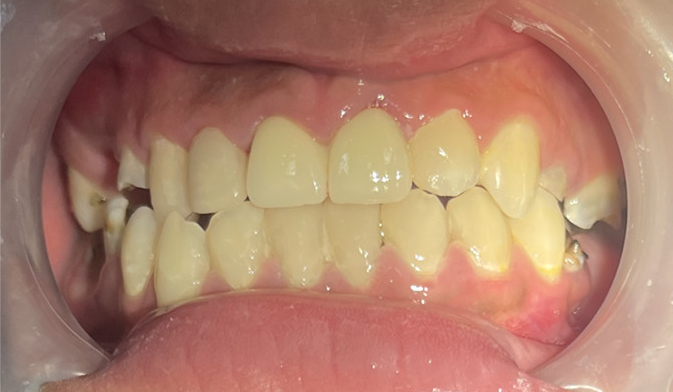

近日,广州市花都区人民医院口腔科通过规范的诊疗流程,为一名18岁男孩完成牙齿“蜕变”,让其重拾自信笑容。

这名男孩就诊时满口黑牙,颜值大打折扣。广州市花都区人民医院口腔科结合放射检查、内科治疗、外科干预及修复重建等诊疗环节,制定了“拍片检查—牙周治疗—拔牙—根管治疗—桩冠修复”的系统性方案,后续还将为其缺失牙进行种植修复。